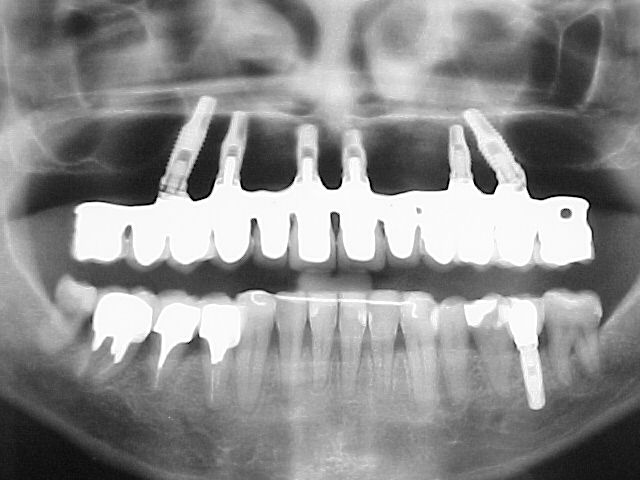

RX panorâmico posterior ao tratamento

Caso de reabilitação estética e funcional complexa por meio de um sistema de PROTOCOLO EM METALO-CERÂMICA com dentes separados, cimentados individualmente e apoiados sobre seis implantes em maxila, com gengiva artificial caracterizada em resina acrílica termopolimerizável.

Plano de tratamento: 1) Tratamento ortodôntico para a mandíbula, com o propósito de reverter (alinhar e nivelar) a má-oclusão descrita acima; 2) Implantes maxilares como base de sustentação de prótese fixa, com gengiva artificial para compensar a reabsorção óssea ocorrida ao longo dos anos; 3) Reposicão do elemento ausente na mandíbula com implante e coroa metalo-cerâmica; 4) Próteses unitárias diversas sobre raízes naturais; 5) Reanatomizações e restaurações diversas em resina composta direta.

Conceito: Barra Metálica com núcleos contornados por acrílico imitando o tecido gengival (vista oclusal)